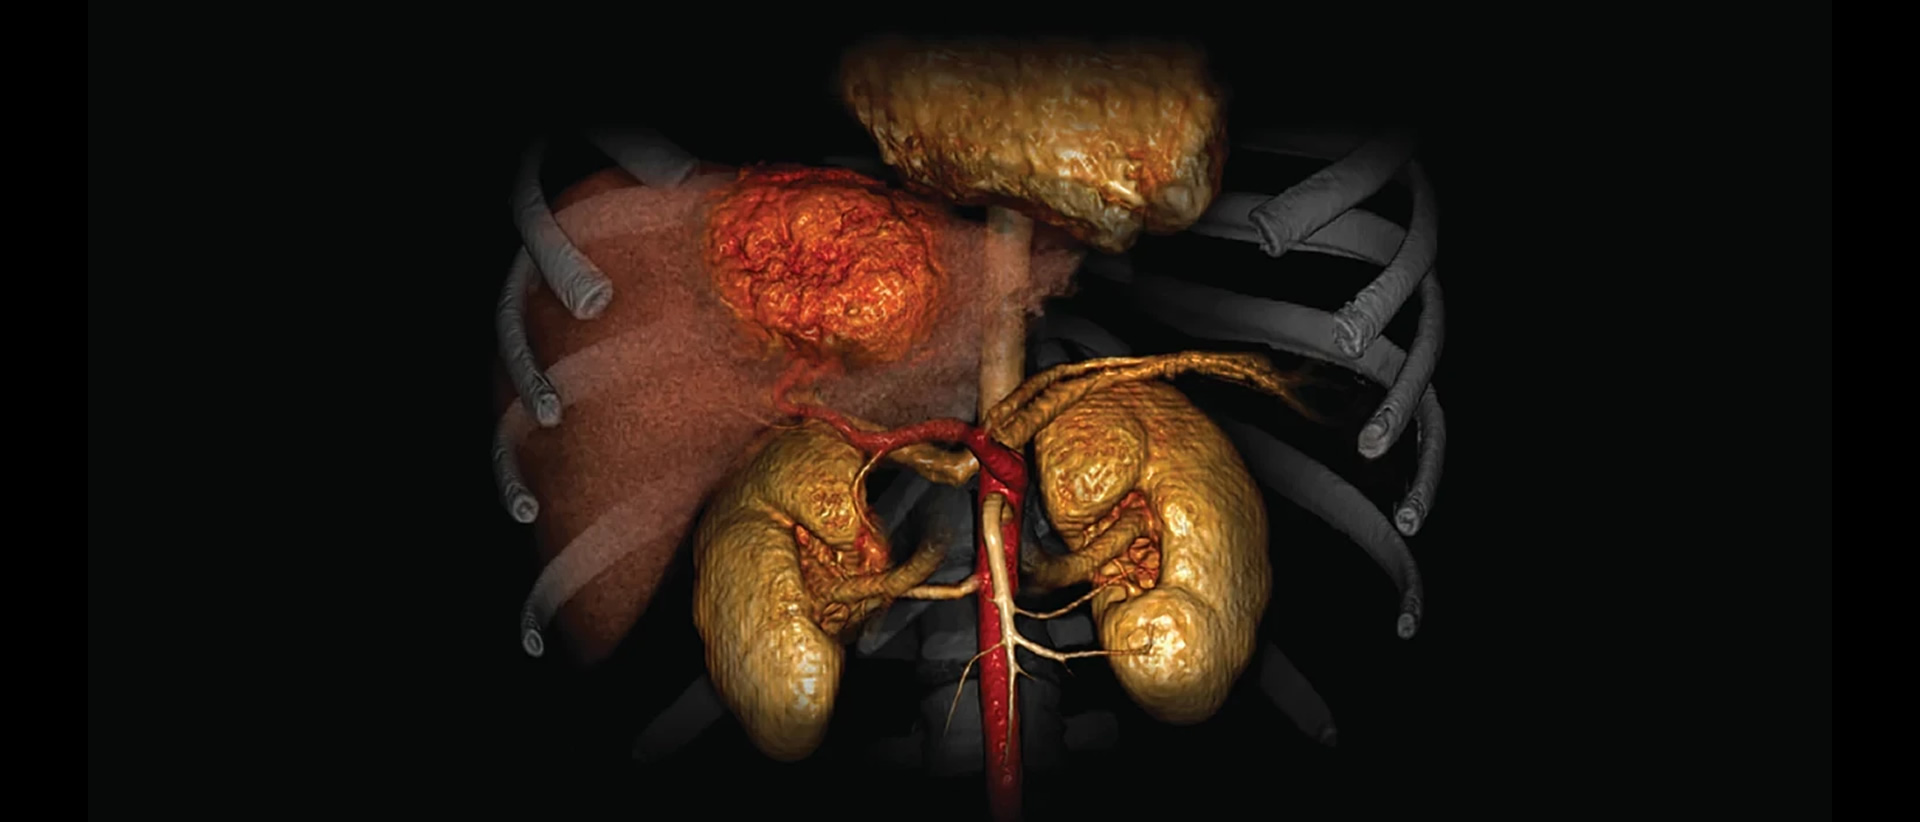

Artículos orientados a Médicos Radiólogos con casos reales de nuestras clínicas